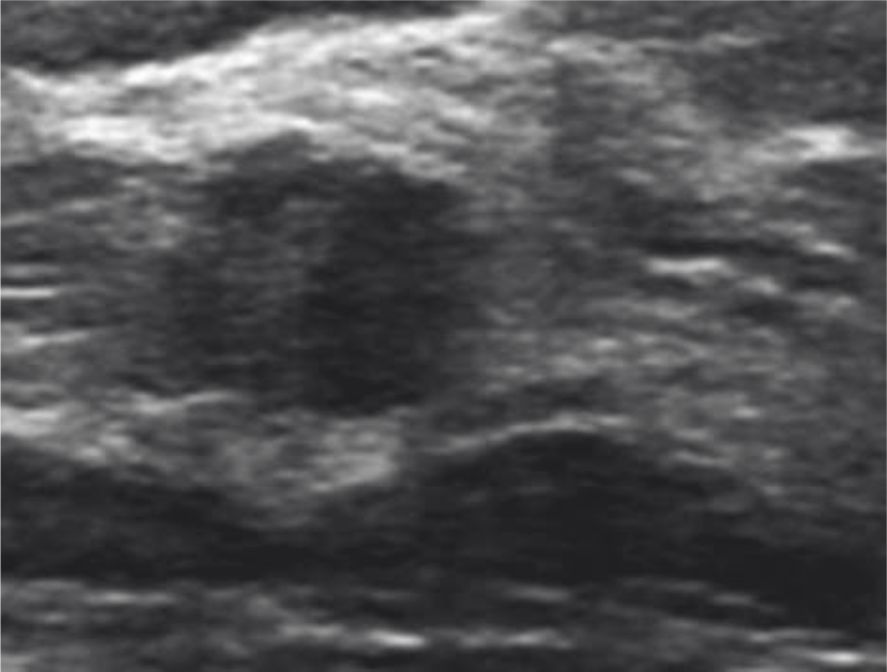

Figura 1

Ecografía de alta resolución.

Muestra un nódulo sólido, hipoecoico de 8 mm de diámetro, de márgenes microlobulados categorizados como ACR BI-RADS® 4B. Histología Carcinoma Invasivo de Tipo No Específico (NOS).

Figura 2

Nódulo sólido,

ovoideo de contornos circunscritos con extensión intraductal categorizado como ACR BI-RADS® 4B. Histología Fibroadenoma